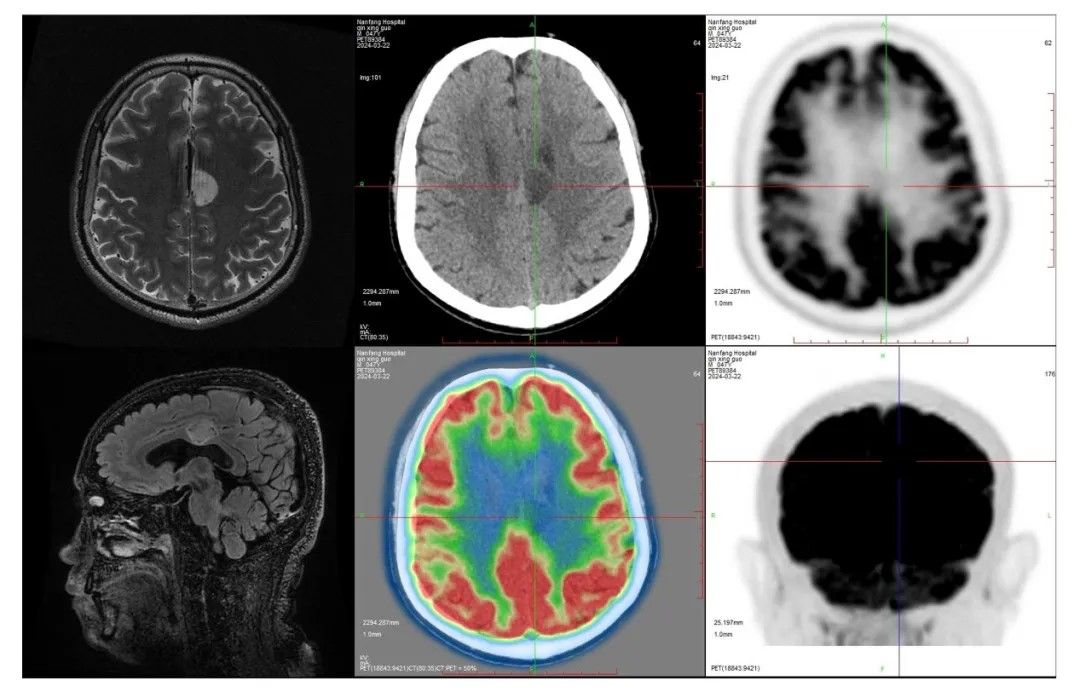

47岁的李先生(化名)六年前确诊为癫痫,长期使用多种抗癫痫药物治疗效果不佳。近日,他来到南方医院神经外科龙浩教授门诊就诊,经医院“癫痫MDT”会诊评估,左侧中扣带回的类圆形异常信号影,高度怀疑为致痫灶。

患者术前检查提示左侧中扣带回类圆形癫痫灶

病灶位于大脑深部,邻近重要功能区,传统的显微手术切除有相当高的风险,如脑功能区和皮层静脉损伤可能会导致术后偏瘫和脑肿胀等严重并发症。相比之下,激光消融手术有望实现既消融病灶又不损伤周边结构的目标。